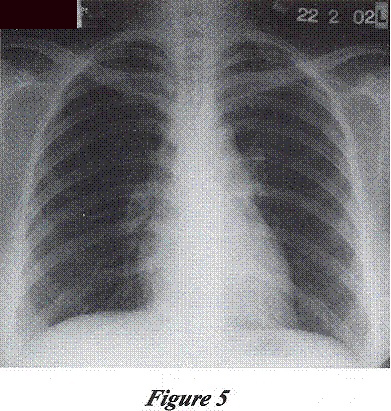

Patient attended Chest Clinic for supervised anti-TB treatment. She presented with mild cough and was afebrile. Her liver function further improved. CXR showed improving lung shadows (Figure 3).